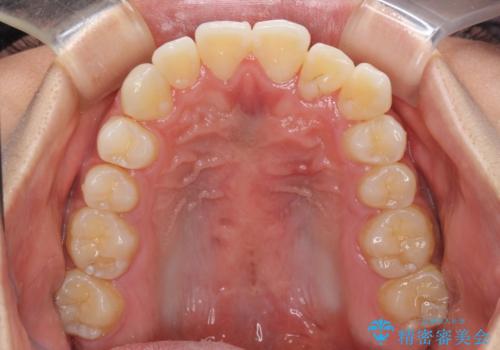

八重歯と奥歯のクロスバイト 上顎骨を拡大してインビザラインで矯正

- 八重歯を気にして来院された患者様です。

八重歯が著しいため、抜歯矯正も視野に入れて検討しましたが、臼歯の咬合関係は正常に近かったので、非抜歯矯正で進める方針としました。

上顎骨の幅が狭く、奥歯がクロスバイトとなっていたため、急速拡大装置を用いて上顎骨を側方拡大し、八重歯を収めるスペースを獲得しつつクロスバイトを改善することとしました。

上顎骨を思い通りに拡大できたため、当初の計画通りに非抜歯矯正で仕上げることができました。